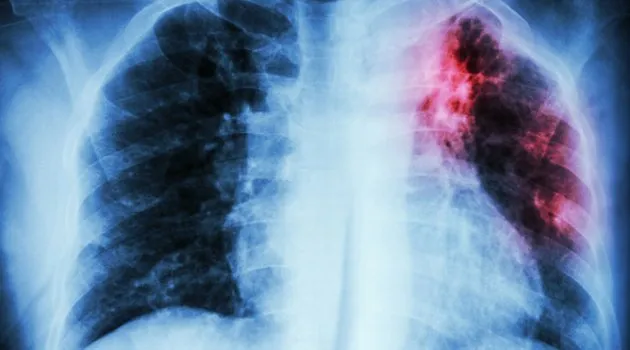

Hala etkili bir hastalık olan verem (tüberküloz), hala her yıl 2 milyon kişinin ölümüne sebep oluyor.

Verem, bir başka deyişle tüberküloz, günümüzde artık tedavi edilebilir olmasına rağmen hala çok sayıda kişi bu hastalık nedeniyle hayatını kaybediyor? Bunun nedeni ise hastalığın zamanında tespit edilememesi ve tam tedavinin uygulanmaması. Veremin dünyanın en yaygın enfeksiyon hastalığı olduğunun altını çizen Acıbadem Fulya Hastanesi Göğüs Hastalıkları Uzmanı Prof. Dr. Reha Baran, bu hastalıktan 2020?yılına kadar 30 milyon kişinin hayatını kaybedeceğinin öngörüldüğünü söylüyor. Hastalıkla mücadelede yapılan en büyük hatanın ise tedaviyi erken bırakmak olduğunu belirten Prof. Dr. Reha Baran, her hastanın en az 10 kişiye de mikrobu bulaştırdığına da dikkat çekiyor.

Verem binlerce yıldır var olduğu bilinen bir hastalık. Zengin-yoksul, genç-yaşlı demeden herkese bulaşabiliyor. En çok akciğerde olmak üzere tüm organlarda hastalık yapıyor. Tedavisiz bırakılırsa ya da kötü tedavi edilirse, öldürücü olabiliyor. Göğüs Hastalıkları Uzmanı Prof. Dr. Reha Baran, ?Verem mikrobu ne kadar tedavi edilirse edilsin, verem basilinin bir kısmı vücutta ölü olarak kalıyor. Verem mikrobu alan bir kişi o hastalığa hemen yakalanmayabiliyor, ömrünün bir döneminde bu mikrop aktif hale gelebiliyor? diyor.